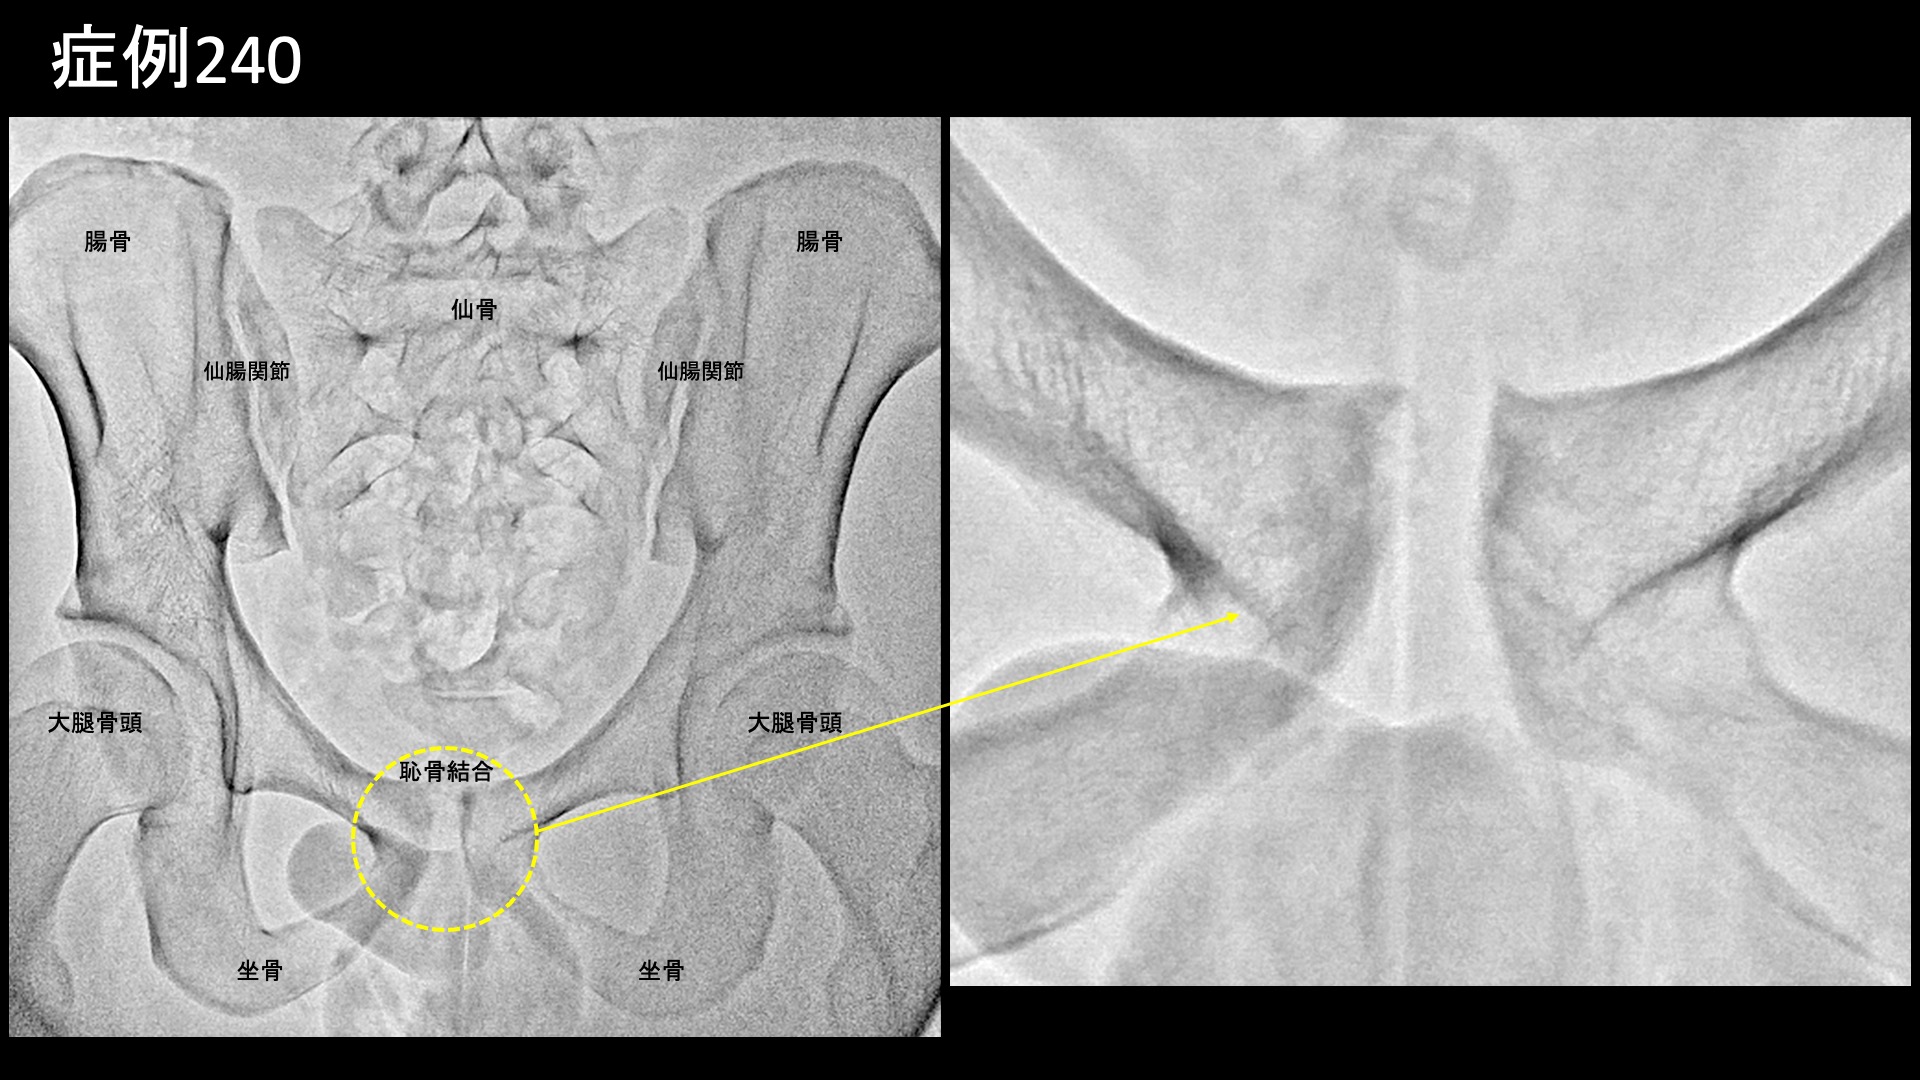

股:変形性股関節症など 【10代:男性】恥骨が痛くて走れない、スポーツが原因で生じた恥骨結合炎に対するモヤモヤ血管治療(恥骨結合炎) 2025.09.26 鴨井院長による動画解説 受診までの経過 スポーツが原因で、半年前から恥骨が痛むようになりました。日常生活では問題ないものの、ランニングで痛み走れなくなってしまいました。キック動作でも悪化しました。下腹部痛はなく、あくまでも恥骨に限局した痛みでした。MRI検査の結果、恥骨結合炎と診断されました。体外衝撃波治療や鍼治療を受けましたが改善しませんでした。十分安静療養をしてきたにもかかわらず、いつまでも治らないことから当院を受診されました。 診察時の所見 恥骨結合に一致して圧痛が見られましたが、少し広範囲に及んでいました。レントゲンでは恥骨結合が開大しており、結合面の骨表層は不整でした。MRI検査では、脂肪抑制T2強調画像において、恥骨結合周囲に高信号を明瞭に認めました。画像所見からは強い炎症が示唆され、日常生活で症状を生じても不思議ではない程度でした。治療適応と判断し、モヤモヤ血管(病的新生血管)に対する運動器カテーテル治療(微細動脈塞栓術)を受けていただきました。 治療の所見 血管造影を行うと、恥骨結合周囲に一致してモヤモヤ血管が濃染像として描出されました。治療後は画像上速やかに消失しました。その他複数個所の治療を行い終了しました。尚、治療時には恥骨結合における再現痛も確認できました。 *再現痛とは、薬液投与時に普段の痛みが一定程度再現される現象です。責任血管の同定のための参考とします。 治療後の経過 治療後2週間、激しい動作は控えていたため、まだ良くなっているかどうかはわかりませんでした。恥骨における圧痛は過敏さが無くなったものの、まだ比較的広範囲に認められました。治療後1ヶ月、走った後に少し違和感があるものの、ダッシュしてみても痛まなくなりました。患部を自分で押してみましたが痛くありませんでした。診察では、圧痛は強度・範囲とも大幅に減っていました。経過良好でした。その後、下半身の筋力トレーニングをした際に痛みが強くなることはあったものの、順調に経過し、治療後6ヶ月時点でもほとんど痛みなく過ごせているとのことでした。典型的な恥骨結合炎の症例でした。早期から改善し、再発なく経過されていて何よりでした。 【70代:男性】夜間痛がその日のうちに改善!強い炎症を伴った変形性膝関節症に対する運動器カテーテル治療(変形性膝関節症) 前の記事 【80代:男性】火が出るような痛みに襲われ夜も寝られず・・発症1ヶ月の頭部/顔面に生じた帯状疱疹後神経痛(帯状疱疹後神経痛) 次の記事